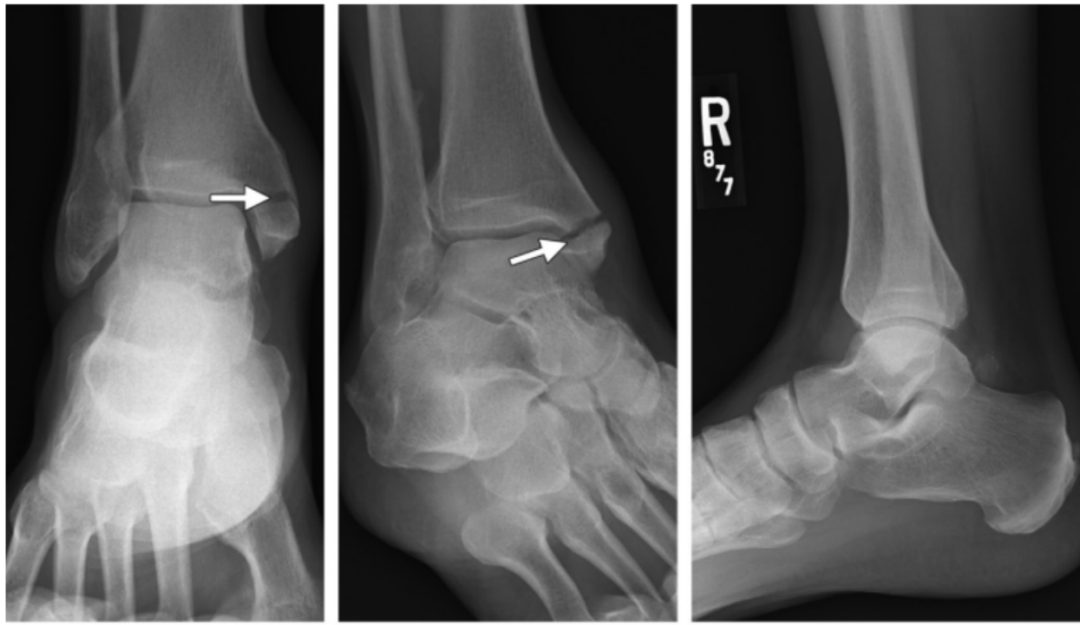

I 度:首先发生的是三角韧带的断裂或者内踝的撕脱骨折。

I 度损伤 X 线显示:内踝水平骨折;侧位 X 线片显示后踝完整。这种损伤与旋前外展 I 度非常相似。

Ⅱ 度:距骨外旋力量继续作用于下胫腓关节,下胫腓前韧带和骨间韧带或韧带附着点撕脱骨折。

II 度损伤 X 线显示:内踝间隙增宽,提示三角韧带断裂;胫腓骨间隙增宽,提示下胫腓前联合断裂。

Ⅲ 度:腓骨骨折发生于胫骨远端关节面以上水平,甚至可以位于腓骨近端即 Maisonneuve 骨折,骨折线从前上方斜向后下方,即与旋后(内翻)外旋骨折相反。

III 度损伤 X 线片显示:内踝骨折和腓骨近端螺旋形骨折;胫腓骨间隙增宽;侧位片显示腓骨骨折,后踝无骨折。

Ⅳ 度:最后发生下胫腓后韧带断裂,或其胫骨附着点的撕脱骨折(Volkmann 骨折块)。

IV 度损伤 X 线片显示:内踝骨折;胫腓骨间隙增宽,提示下胫腓联合断裂,腓骨骨折位于下胫腓联合水平上;侧位片显示胫骨向前移位和后踝撕脱骨折。